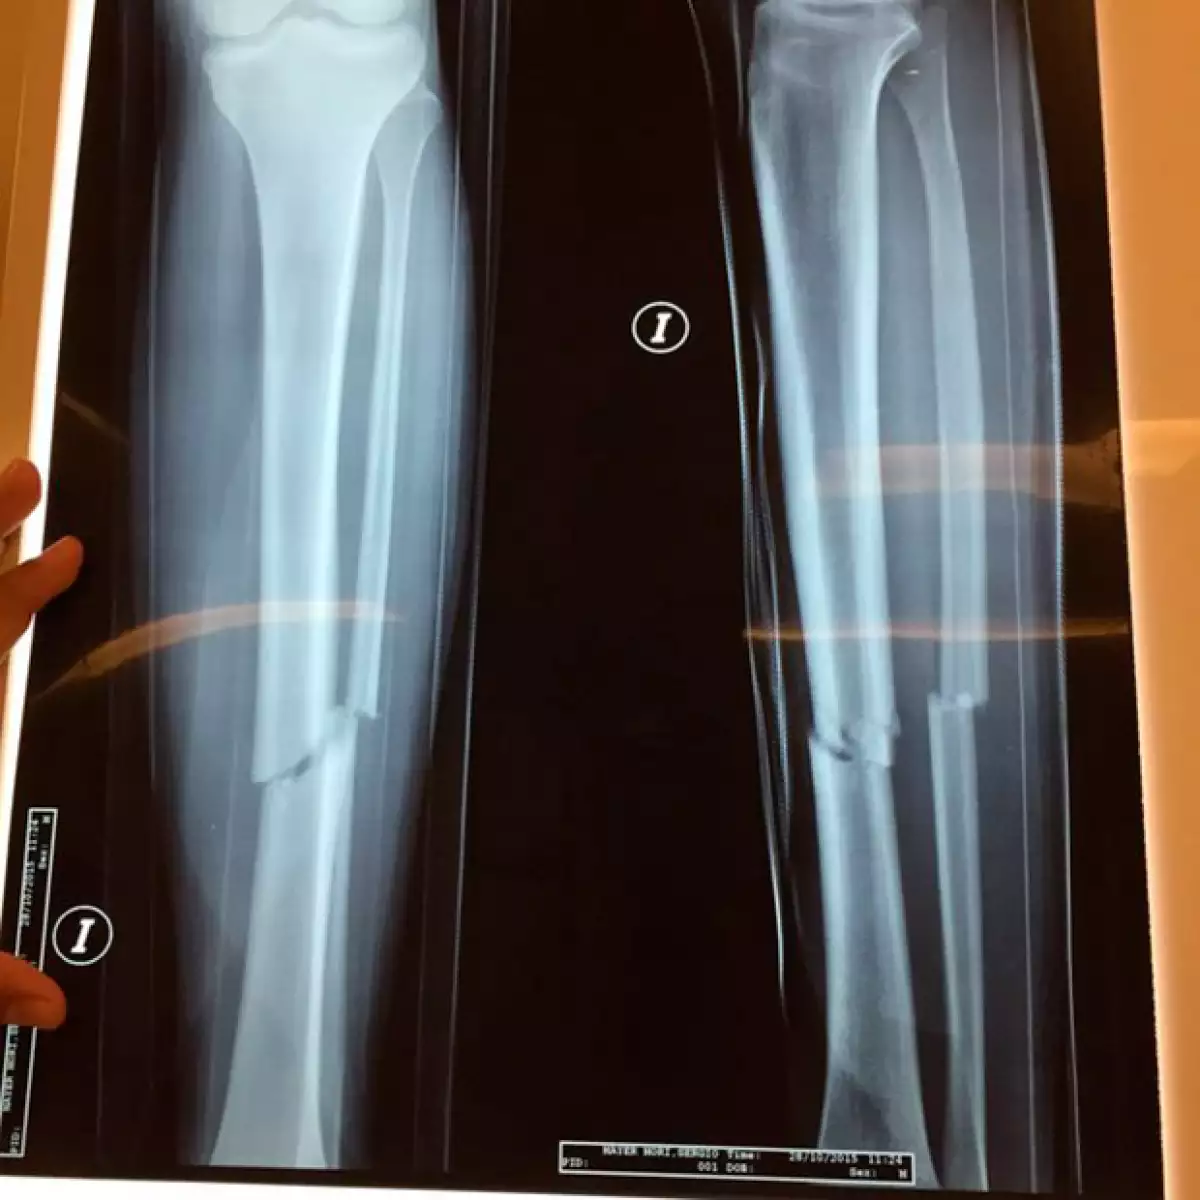

Sergio Mayer Mori sufrió un accidente en motocicleta la semana pasada en Cholula, Puebla, la cual le originó una fractura de tibia y peroné.

Horas más tarde, el propio Sergio Mayer publicó que su hijo fue intervenido: "Gracias a los que han preguntado del estado de @SMayerMori , ayer entró a cirugía por la fractura de tibia y peroné y está en recuperación (...) Salió todo muy bien gracias a Dios, mil bendiciones por sus deseos y comentarios hacia @SMayerMori".

"Me pusieron cinco clavos, uno va desde la rodillas por todo el hueso, por la médula, hasta el talón", declaró Sergio Mayer Mori a Televisa Espectáculos.